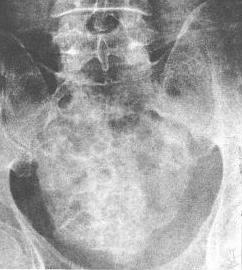

骶骨脊索瘤(平片)

骶骨脊索瘤。示骶骨中央于第1骶孔以下骨质破坏,存留骨质硬化增白,并杂有散在的钙化点。骶骨病变部略膨大,下缘向外隆起。

2.脊柱发生的脊索瘤最多见于骶尾部,患骨明显膨胀,骨内正常的结构消失而呈毛玻璃样阴影,随着肿瘤的发展,肿瘤呈溶骨性缺损。有时可穿破骨皮质,形成边缘清晰的肿瘤性软组织块影,其内可有残余骨质硬化或散在不成形的钙化点。造影可显示直肠、膀胱、子宫等邻近器官或组织受压、推移改变。